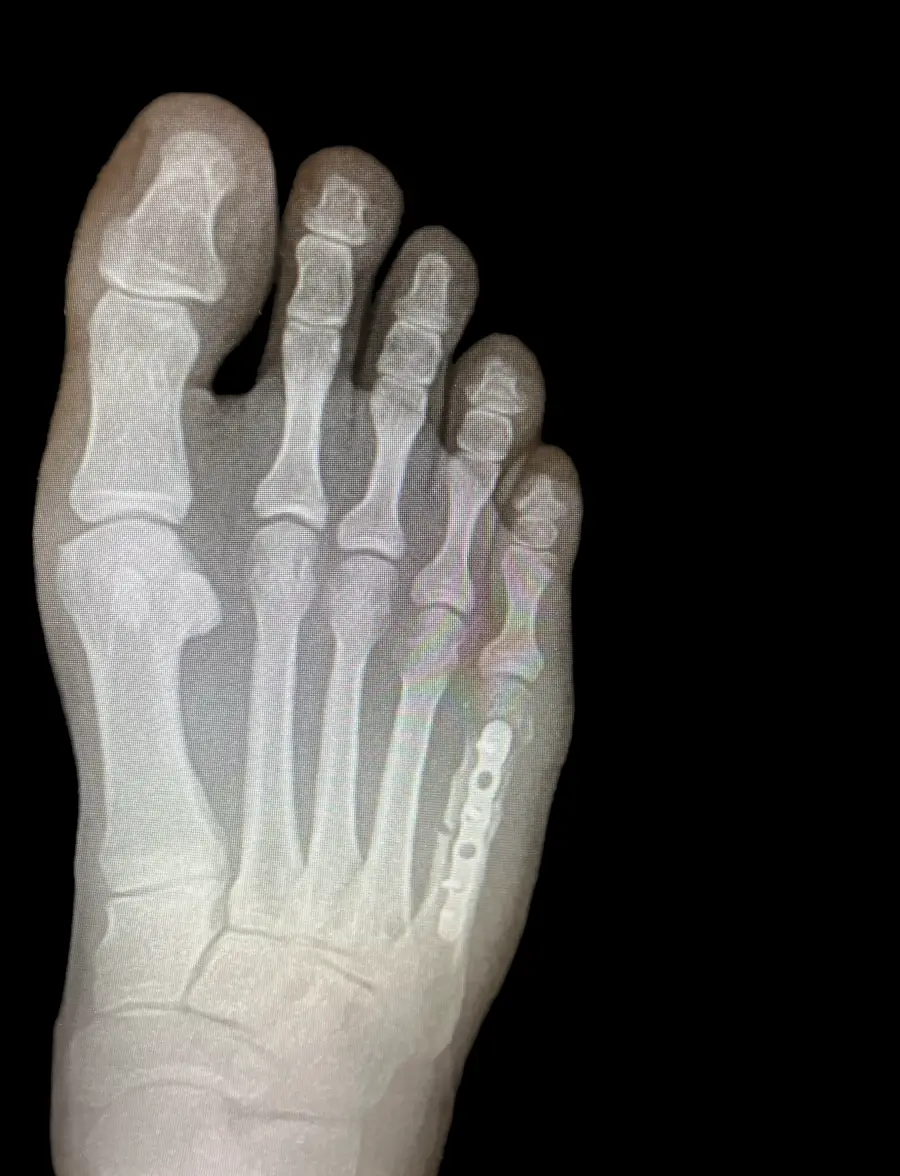

Surgical Intervention at Stepwell Institute is never a “one-size-fits-all” solution. We view surgery as a precise tool used to restore the natural biomechanics of the foot and ankle when non-invasive methods have reached their limit. Our philosophy centers on individualized surgical planning—using advanced imaging to map out the procedure before you ever enter the operating room. From correcting bunions and hammertoes to performing ligament repairs and fracture fixations, Dr. Yakov utilizes techniques designed to minimize trauma to the surrounding tissues, thereby reducing the risk of complications and ensuring a more stable, long-term result for our patients.

• Hardware Removal Surgeries

Our Case Study